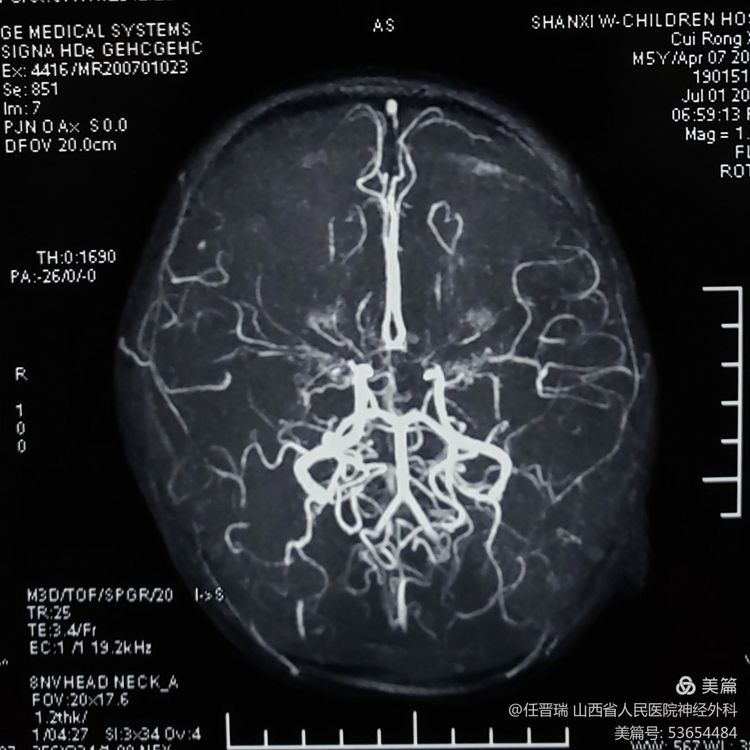

入院3月前颅脑MR: 双侧额顶叶可见多发急性脑梗死灶

3月前颅脑MRA:双侧大脑中动脉闭塞及双侧大脑前动脉闭塞

全脑血管造影:双侧大脑中动脉及双侧大脑前动脉闭塞,颈内动脉末端烟雾样血管形成